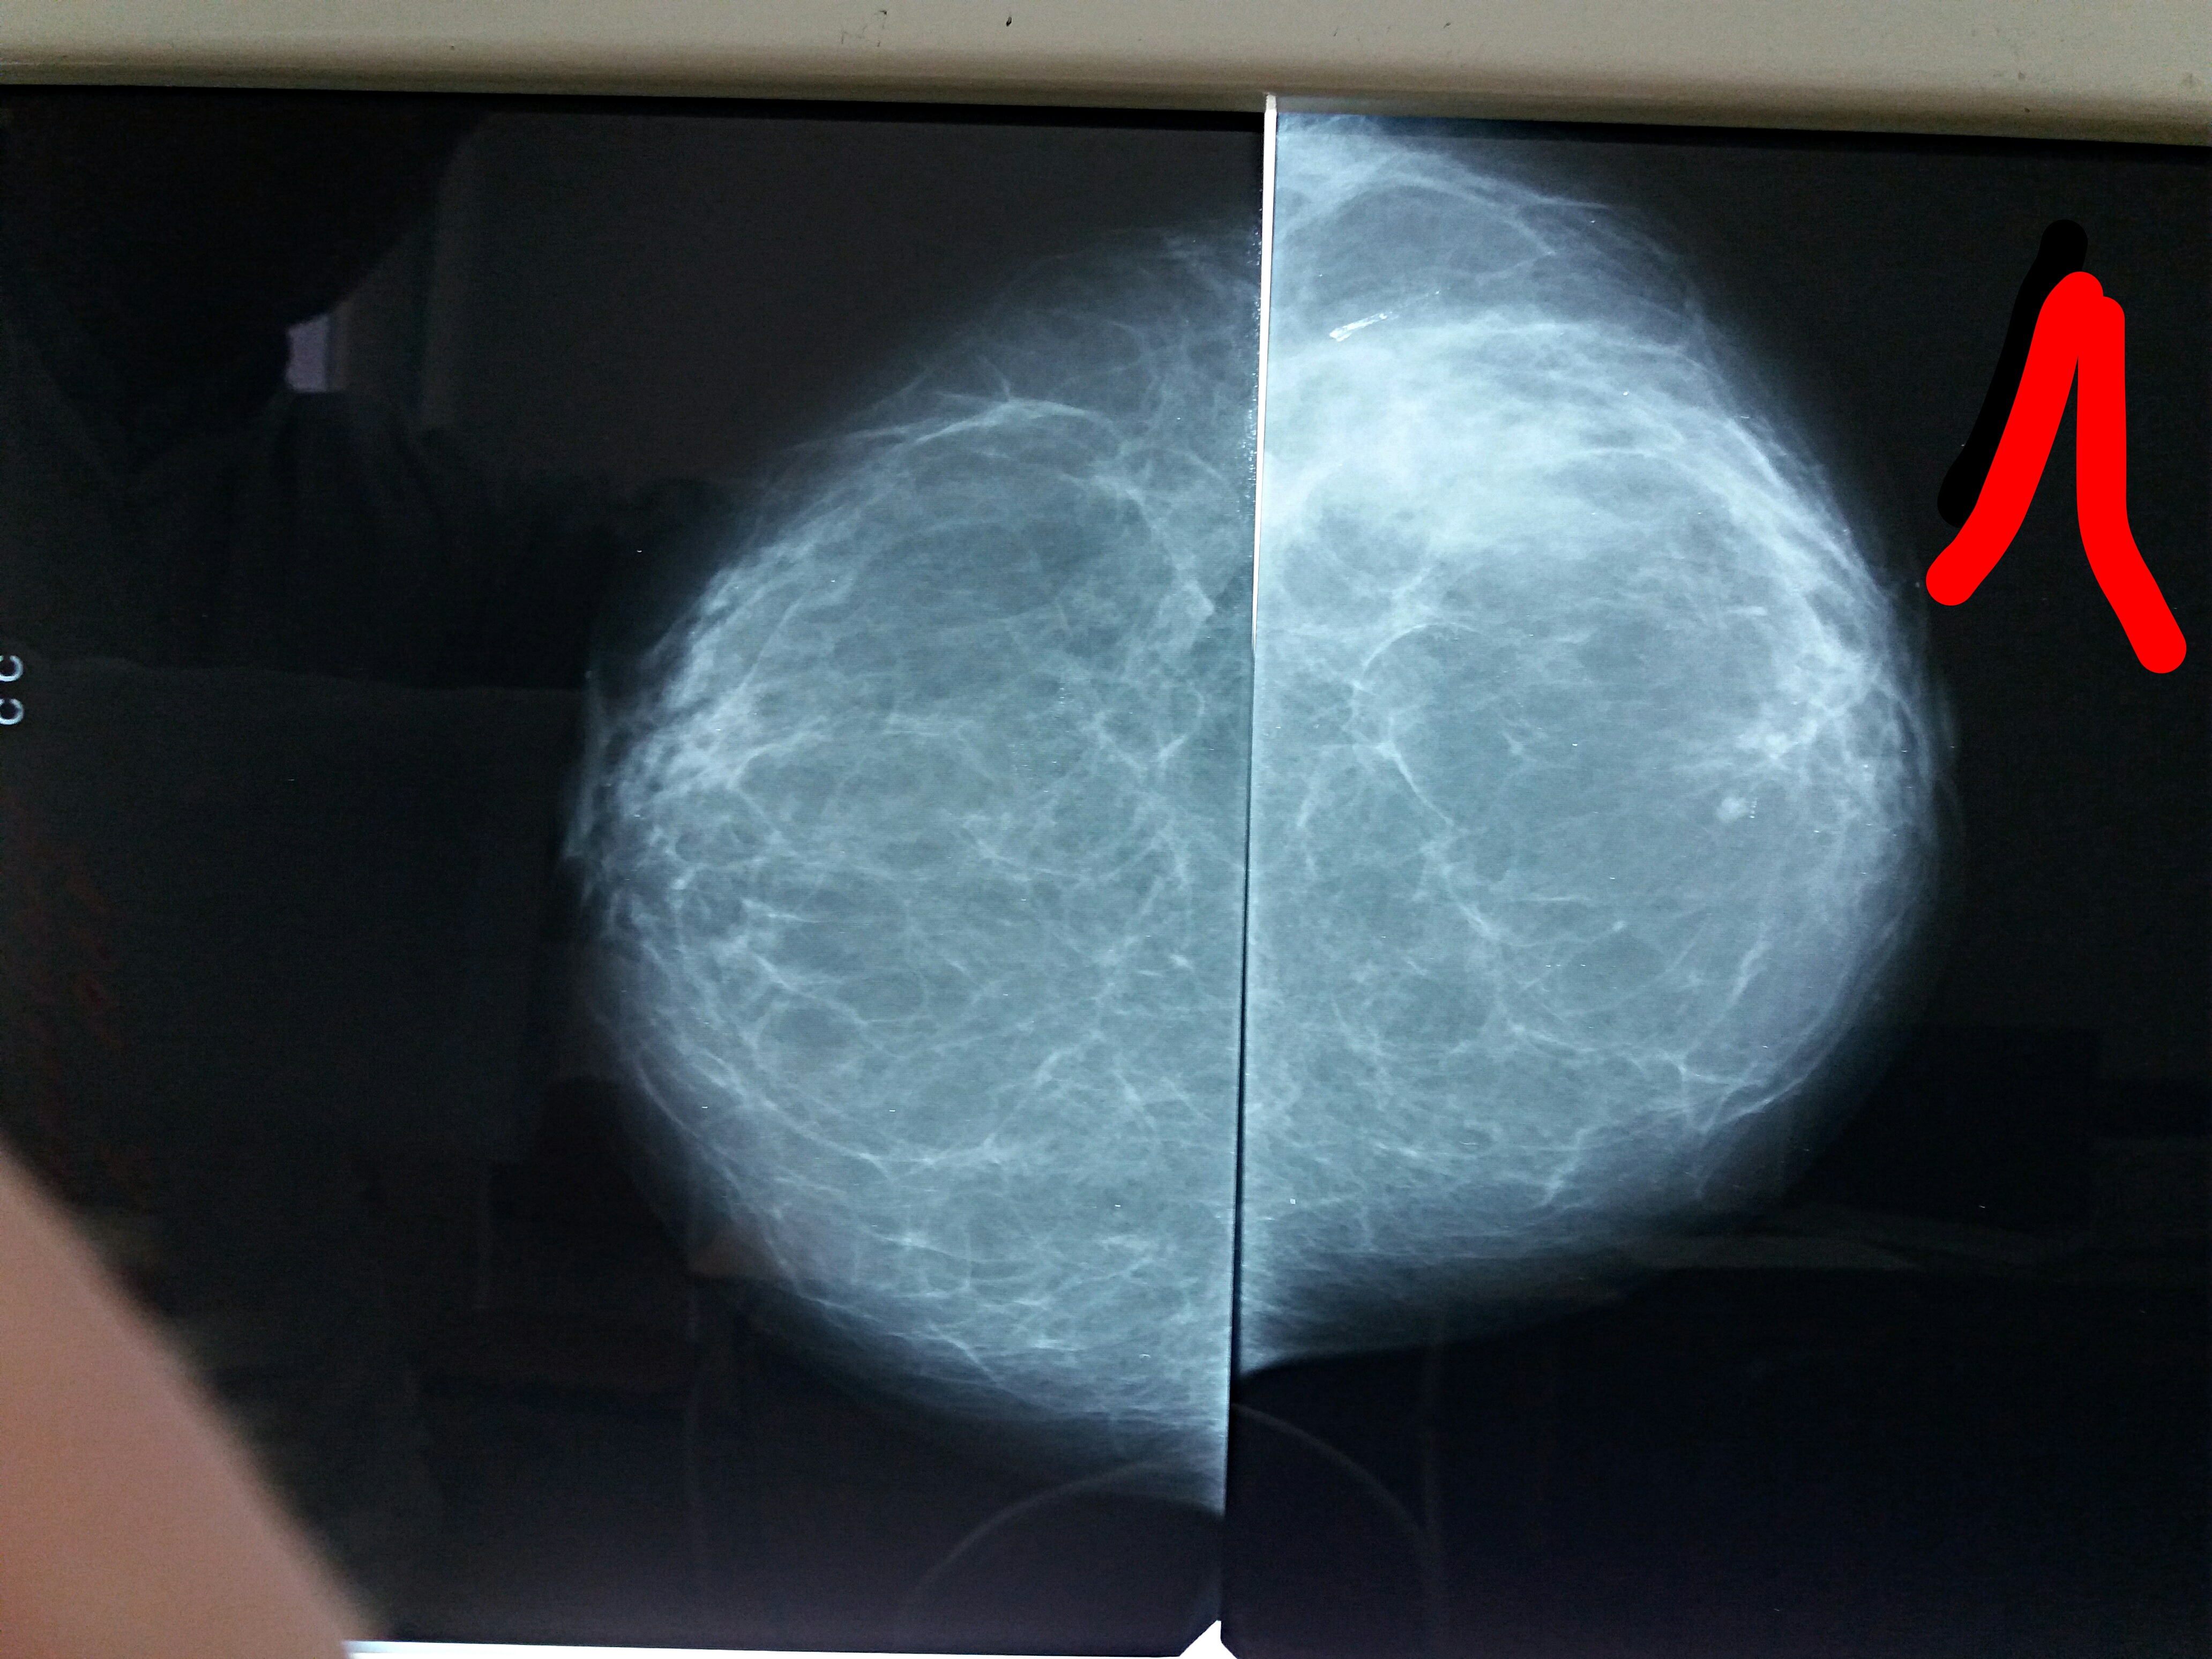

Что такое маммография: важность, процесс и результаты

Раздел: Необычные решения